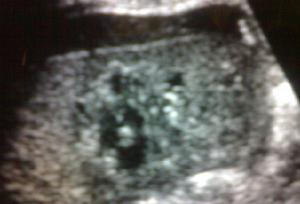

3.腹部CT檢查 CT能確定脾損傷的存在及其損傷範圍,具有非常高的敏感性和特異性。脾包膜下血腫表現為局限性包膜下積血,似新月形或半月形。伴有相應實質受壓變平或呈鋸齒狀。最初血腫的密度近似於脾的密度,超過10 天的血腫其CT值逐漸降低,變為低於脾實質密度。增強CT顯示脾實質強化而血腫不變,形成明顯密度差異,對平掃圖上等密度的血腫乃為重要的補充檢查手段。脾實質內血腫常呈圓形或卵圓形的等密度或低密度區。單一的脾撕裂在增強的脾實質內看到線樣的低密度區,多發性脾撕裂常表現為粉碎性脾,呈多發性低密度區,通常侵及脾包膜,以及伴腹腔積血,脾臟不增強的部分,提示損傷或供應脾臟段的動脈栓塞。脾撕裂傷顯示為脾內帶狀、斑片狀或不規則狀低密度影,多同時伴腹腔積血徵象,脾內血腫密度隨時間而變化,新鮮血腫為等或略高密度,隨時間的延長,血紅蛋白溶解和血腫水容量增高,血腫密度逐漸降低,易於診斷。脾包膜下血腫CT顯示為等或略高於脾密度影,與脾內等密度血腫一樣,CT平掃易於漏診,須做增強CT方能確診。文獻提示約有1%~15%的脾損傷病人在傷後即刻CT掃描所見正常,而48h 後複查CT才能發現脾損傷徵象,一般在3 周左右,少數潛伏期可幾個月或數年。CT掃描不僅對脾損傷的診斷具有敏感性,特異性,且能進一步估計損傷程度,從而指導臨床治療方案的制定,並預測病人的預後。